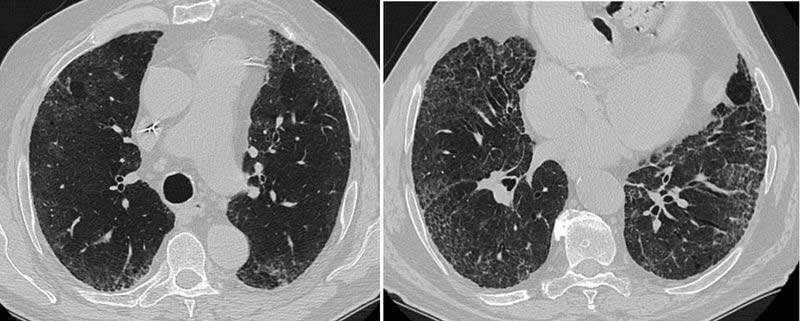

Es gibt vielfältige morphologische Erscheinungsbilder der Erkrankung in der Lunge mit Überlappungen zu anderen Erkrankungen. Die Diagnose in der Computertomographie kann deshalb anspruchsvoll sein. Dabei ist unklar, warum sich die Sarkoidose im Einzelfall so unterschiedlich verhält – abgesehen von der Frage der Organbeteiligung. Die Verlaufsformen werden in akut oder chronisch eingeteilt. Akute Formen der Sarkoidose beginnen häufig mit Gewichtsverlust, Abgeschlagenheit, Nachtschweiß oder Temperaturen 37,5°C bis 37,9°C (subfebril). Die Kombination von Gelenkschmerzen, bläulichem Hautausschlag und Fieber ist als sogenanntes Löfgren-Syndrom bekannt. Entzündungsparameter im Blutserum schließen eine erhöhte Konzentration von Interleukin-2-Rezeptoren ein. Die akute Sarkoidose betrifft neben der Lunge oft weitere Organe, z.B. lymphatische Organe, Milz, Leber und Knochenmark. Akute Verlaufsformen ohne Beteiligung der Milz tendieren zur Spontanheilung (Spontanremission). Wiederauftreten (Rezidive) manifestiert sich hingegen meistens mit akuten Symptomen.

Die chronische Form verläuft langsamer und ist medikamentös schwieriger zu therapieren. Besonders wenn das Herz oder das Gehirn beteiligt sind. Ferner kann es bei einer chronischen Lungenfibrose zu massiven Organschäden kommen – besonders bei der fibrozystischen Verlaufsform. Eine Nierenbeteiligung kann ohne Therapie zum Nierenversagen führen.

Die Diagnose erfolgt anhand: typischer Hautveränderungen, Lymphknotenvergrößerungen, morphologischer Veränderungen der Lunge in der Computertomographie und / oder des Nachweises von Sarkoidose-Granulomen im Gewebe. Besonders die Abgrenzung zu anderen Systemerkrankungen kann erhebliche Probleme aufwerfen, auch nach histologischer Abklärung. Das spezialisierte ILD-Board entscheidet interdisziplinär, welche diagnostische Methode wir im Einzelfall heranziehen.